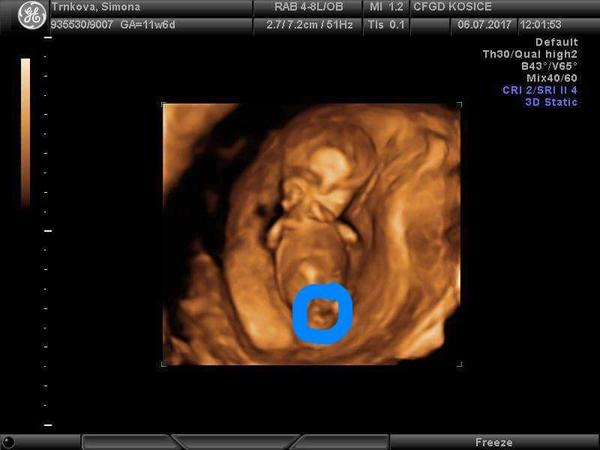

no takto to vyzera vselijako, ja si teda este netrufam povedat co to moze byt. doktora si sa nepytala? ci ti povedal, ze je este skoro a chces to nejako odhadnut sama? mozno to vyzera na chlapceka ale ked je to v tom kruzku tak je to take dost skreslene :/

Kolky tyzden to je? No podla toho vtom kruzku to mozno aj tak vypada,ale lepsia by bola foto bez toho modreho kruzku🙂